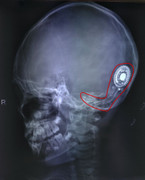

Lần đầu tiên được nghe tiếng thấy tiếng nói và âm thanh cuộc sống nhờ cấy điện cực ốc tai, cô bé 7 tuổi ở Đồng Nai khiến mọi người chứng kiến trào nước mắt vì xúc động.